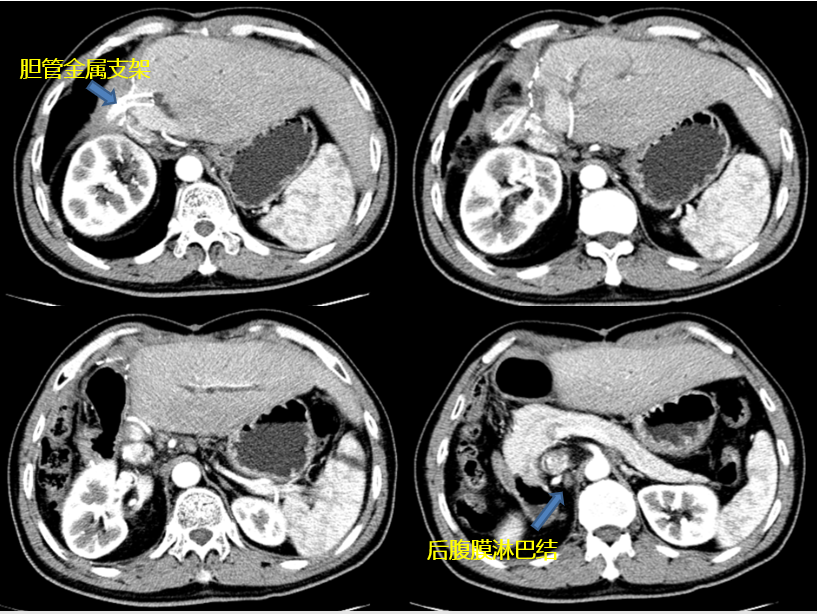

2017年7月再次出现梗阻性黄疸,影像学提示吻合口复发,腹膜后淋巴结转移。予PTCD(经皮肝穿刺胆管引流)下金属支架植入,术后给以信迪利单抗200mg q3w,共9周期。期间CA199直线下降(图2),影像学可评估的后腹膜淋巴结逐渐缩小,失去活性,疗效评价持续完全缓解(CR;图3,图4)。

图4. 信迪利单抗治疗26个月后,于2019年12月复查结果:持续无瘤状态(NED)